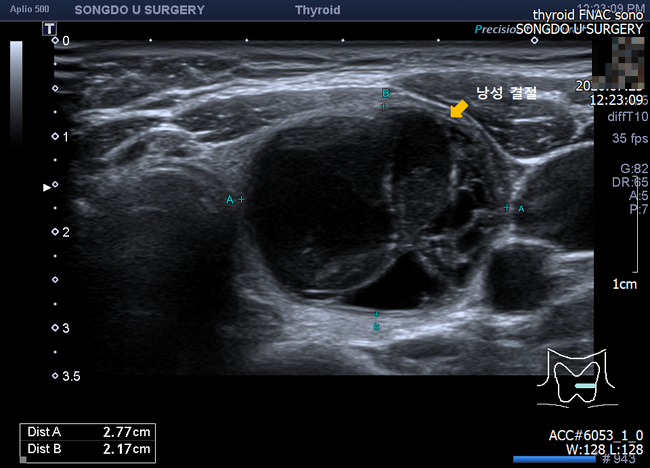

양성종양이 악성으로 바뀌는 경우는 개개인의 약 5%에 해당하며, 갑자기 크기가 커지거나 출혈이 발생하는 경우에는 갑상선 결절 고주파 시술, 목종양 치료, 세밀한 검사가 필요할 수 있습니다. 오늘은 인천외과 추천 미웰유외과에서 갑상선 통증, 갑상선 결절 고주파 시술에 대해 알아보겠습니다.갑상선 결절 의심 증상은?

대표적으로 목에서 느껴지는 이물감, 압박감, 통증, 손으로 닿는 응어리 등이 갑상선 결절 증상에 해당합니다. 양성 종양이 있다고 하더라도 일반적으로 갑상선의 역할에 악영향이 없지만 혹의 크기가 매우 크면 주위 조직을 눌러 답답함, 통증을 동반할 수 있습니다. 약 30%가 초음파 검진에서 양성 종양이 발견되고 목에 혹을 만져 검사를 진행하는 경우에는 약 5%가 암 판정을 받는 것으로 알려져 있습니다.갑상선 통증을 방치하지 마세요!

하지만 단순히 수혹(낭포)인 분들은 주사기를 사용해서 물을 빼면 크기가 작아지고 심지어 없어지는 경우도 있습니다. 또한 과거에는 외과적인 절차에 따라 절개를 진행하여 종양을 제거하였으나 오늘날에는 최소 절개 부분 마취로 미세침을 사용한 갑상선 결절 고주파 시술로 통증과 부담이 적은 종양 제거 및 크기 감소를 기대할 수 있습니다.갑상선 통증 인천외과 추천 미웰유외과에서!